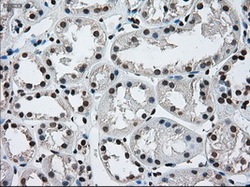

- Immunohistochemical staining of paraffin-embedded pancreas tissue using anti-ERCC1 mouse monoclonal antibody. (Dilution 1:50).

- Submitted by

- LSBio (provider)

- Enhanced method

- Genetic validation

- Main image

- Experimental details

- Immunohistochemical staining of paraffin-embedded Carcinoma of pancreas tissue using anti-ERCC1 mouse monoclonal antibody. (Dilution 1:50).